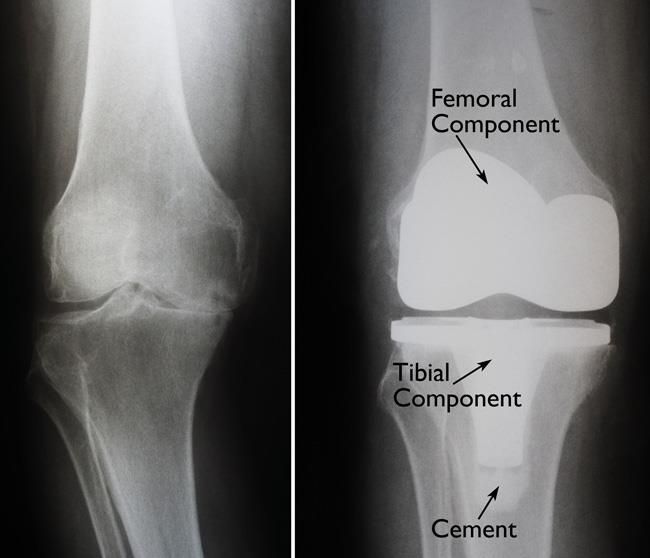

Knee replacement, also known as knee arthroplasty, is a surgical procedure to replace the weight-bearing surfaces of the knee joint to relieve pain and disability. It is most commonly performed for osteoarthritis, and also for other knee diseases such as rheumatoid arthritis and psoriatic arthritis.